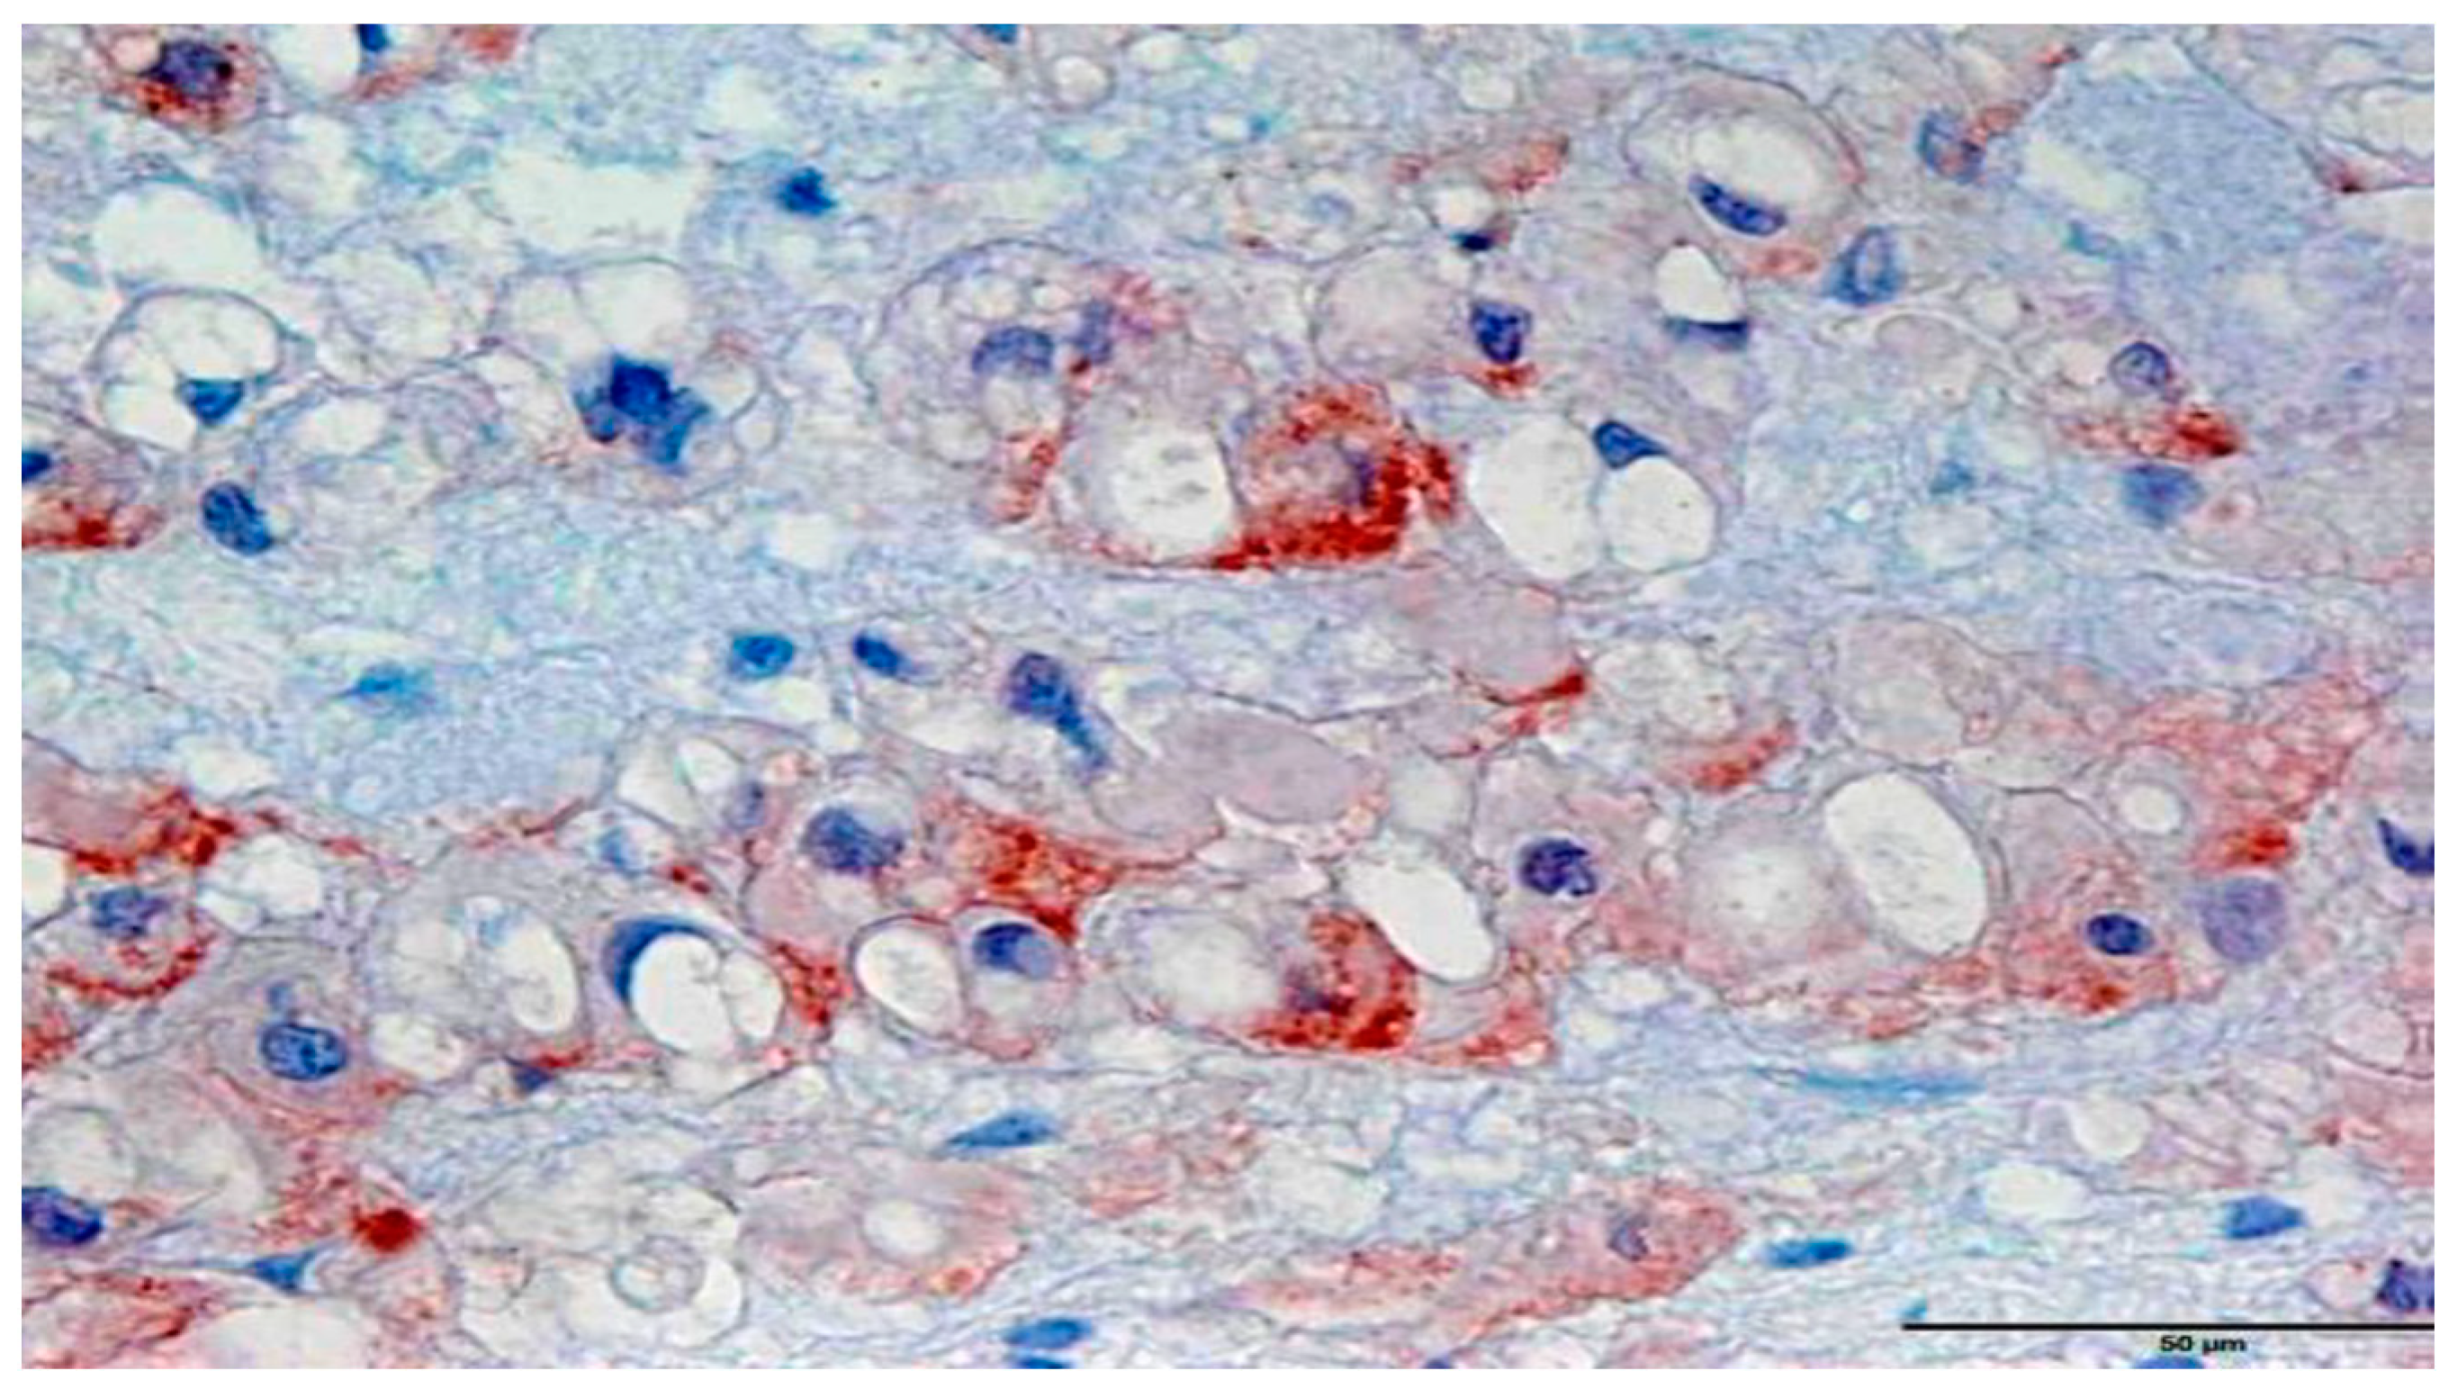

2.4. In Situ Hybridization

3.2. In Situ Hybridization